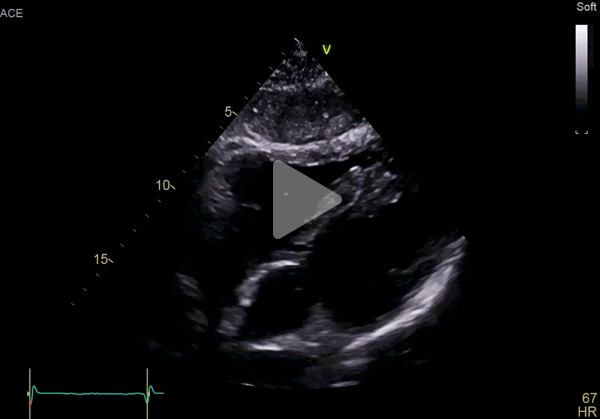

ETT :

- Hypertrophie ventriculaire gauche à prédominance septale (SIVd 12 mm, PPVG 12 mm) sans obstruction de repos, de fonction systolique conservée à 60 % en Simpson biplan. Cinétique homogène, SLG altéré à - 16 % en cocarde

- Profil mitral restrictif

- VD fin de bonne fonction longitudinale

- Pas de dilatation du massif atrial

- Pas de valvulopathie mitroaortique significative. Aorte ascendante non dilatée

- Veine cave inférieure fine respirante. Péricarde sec

Vidéo 2 : PSPA